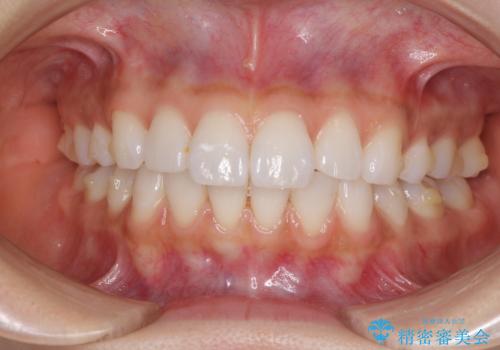

矯正治療の後戻り インビザラインによる再矯正治療

- 以前ワイヤー装置にて行った抜歯矯正の後戻りを気にして来院された患者様です。

前歯のデコボコにより、やや口元が突出した印象となっていたため、口元も引っ込めることとしました。

上下顎前歯に積極的にIPR(歯と歯の間を削る)を行い、インビザラインを用いて治療していくこととしました。

デコボコが解消されるのはもちろんのこと、突出感のあった前歯を引っ込めることができ、患者様には大変満足していただきました。